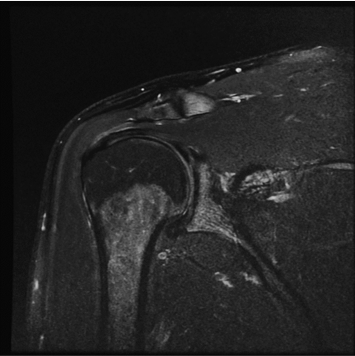

Conventional

384 x 256 (4 NEX)

3:00 minIAI (Innovative AI)

384 x 256 (2 NEX)

1:29 minscan time reduced up to 50%

촬영시간단축, 이미지 품질 향상 모두를 경험 해보세요.